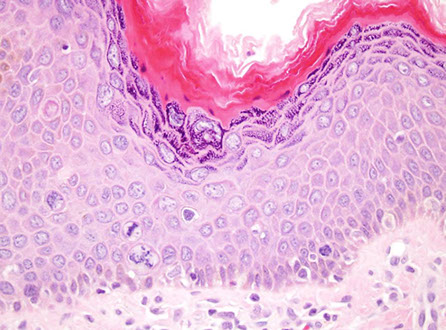

- also see signs of epithelial injury (nuclear irregularity, loss of mucin, epithelial injury, intraep lymphs) but normal crypt architecture, can have slightly inc eos and neuts (though too many neuts suggests superimposed infx colitis)

- surface epithelium stripped (breaks off) from thickened collagen layer

Micro: loss of mucin, epithelial injury, intraep lymphs (similar to collagenous colitis), but lacking the thick subepithelial collagen layer, and does not have neuts